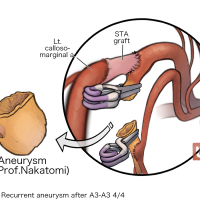

FEN2022シリーズ